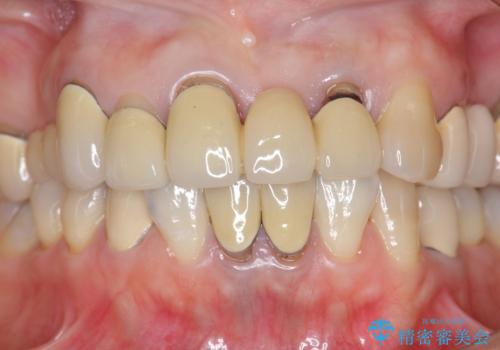

前歯ブリッジのやりかえ

- 前歯の審美障害、見た目の改善を希望され来院されました。

歯肉縁下カリエスも認められるため、挺出を行いセラミックブリッジを審美的に新製します。

- 47万円(仮歯×3・ファイバーコア×2・ジルコニアクラウン×3 歯の挺出)費用は治療当時の料金となります

虫歯が深くなった場合、挺出や歯周外科を行い歯周組織の状態を改善することでより安定した状態で予知性の高いセラミックブリッジを製作することが可能となります。